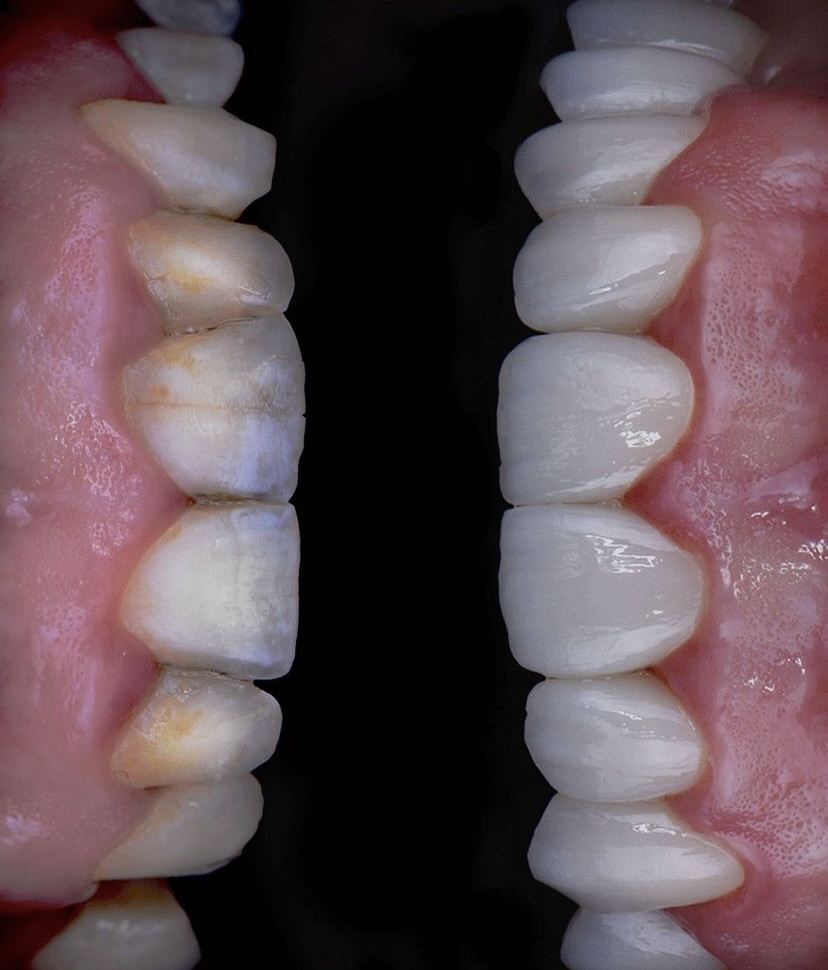

Öncesi̇-Sonrası Resi̇mler

Galeri Öncesi̇-Sonrası Resi̇mler